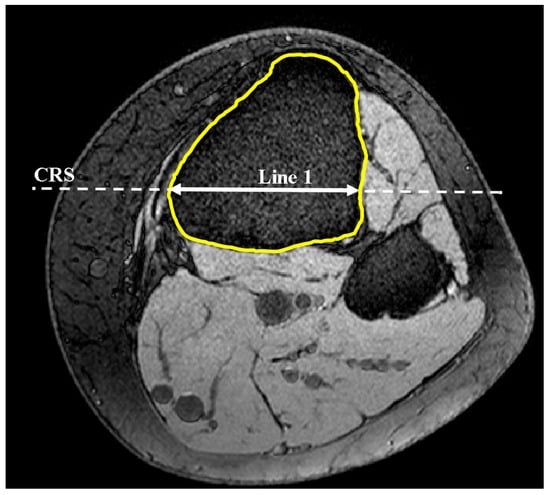

2.1. Medial and Lateral Tibial Slope Measurement Methodology